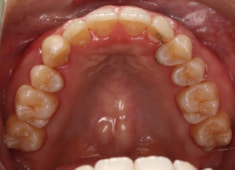

症例紹介

左上3番埋伏歯

治療法:フルパッシブブラケット:T21

治療後(2年後)